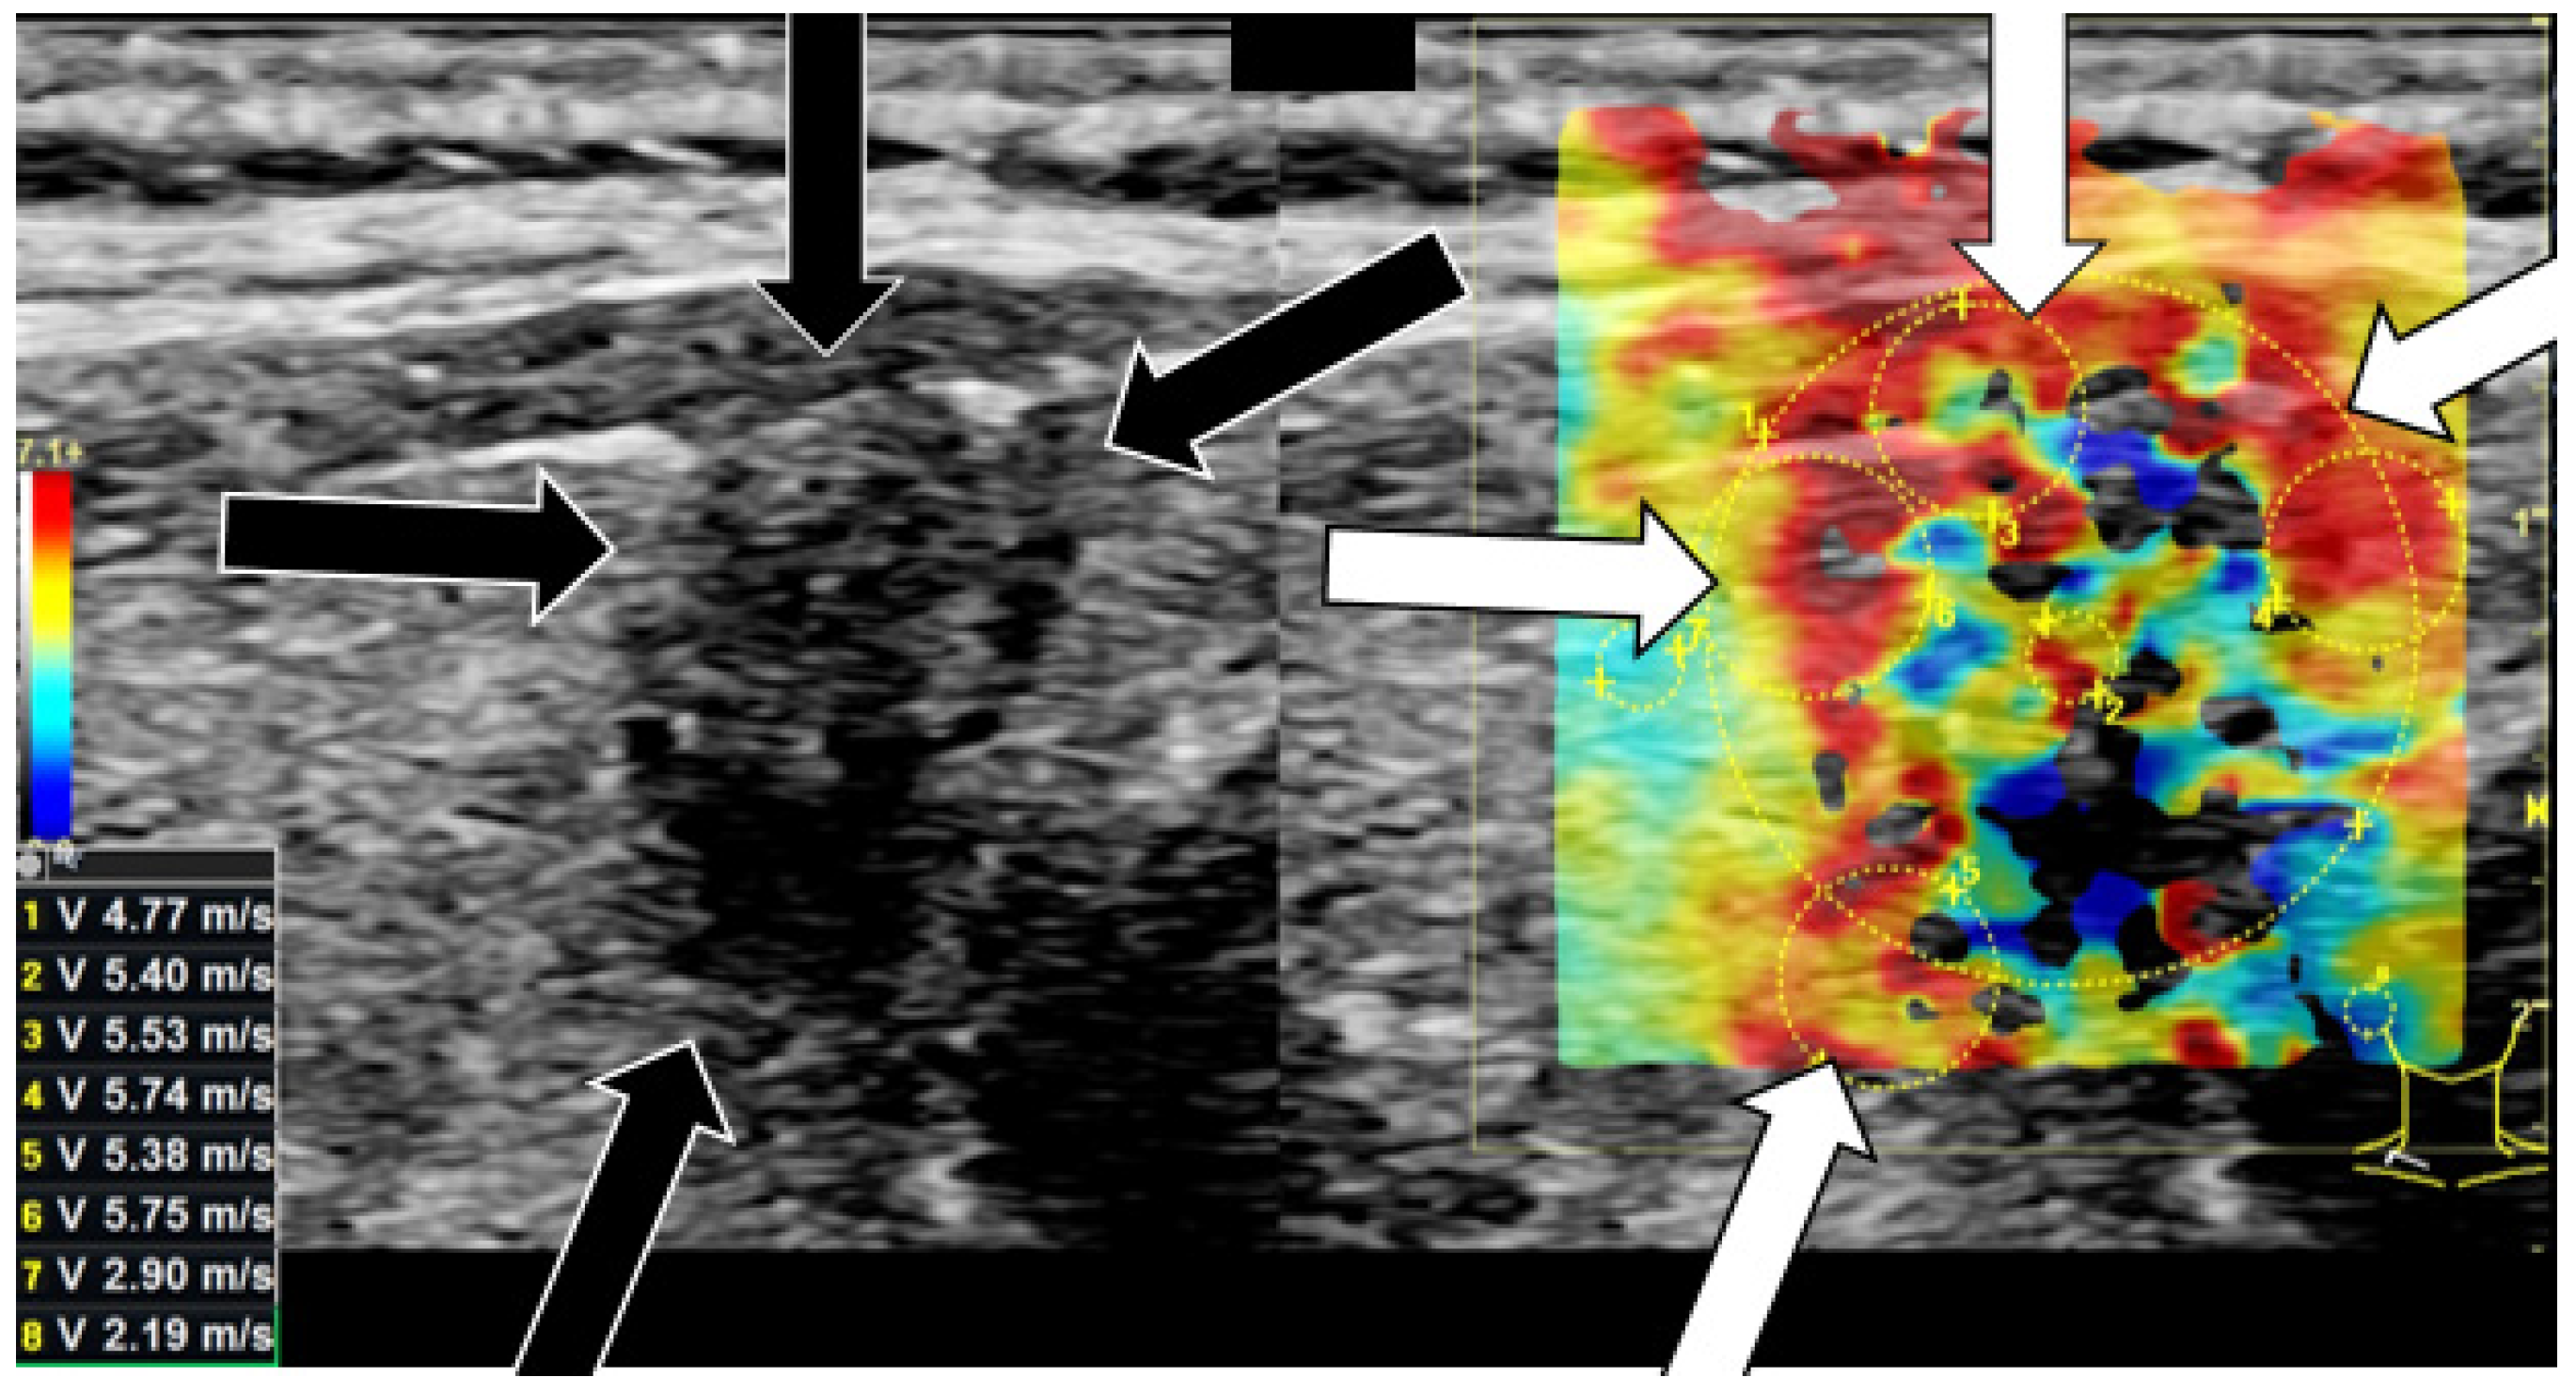

3.2. Shear-Wave Elastography

| Shear-Wave Elastography Measurements | Benign (n ± STD) | Benign (%) | Malignant (n ± STD) | Malignant (%) |

|---|---|---|---|---|

| center [m/s] | 3.50 ± 1.0 | 160.34% | 4.60 ± 1.3 | 226.56% |

| margin [m/s] | 3.49 ± 0.7 | 160.39% | 4.22 ± 1.1 | 207.74% |

| surrounding tissue [m/s] | 2.18 ± 0.8 | 100.00% | 2.03 ± 0.7 | 100.00% |

| center [kPa] | 41.16 ± 25.5 | 260.3% | 69.80 ± 44.8 | 499.61% |

| margin [kPa] | 40.19 ± 14.8 | 254.15% | 60.09 ± 25.1 | 430.16% |

| surrounding tissue [kPa] | 15.81 ± 12.5 | 100.00% | 13.97 ± 6.6 | 100.00% |

| Shear-wave elasto-graphy | marginal cut-off: 4.0 m/s | 90.0 | 3.5 | 75.0 | 81.4 |

| central cut-off: 3.9 m/s | 88.4 | 2.3 | 75.0 | 70.1 | |

| marginal cut-off: 50.7 kPa | 90.8 | 1.1 | 75.0 | 75.3 | |

| central cut-off: 46.9 kPa | 89.2 | 1.0 | 75.0 | 72.2 | |